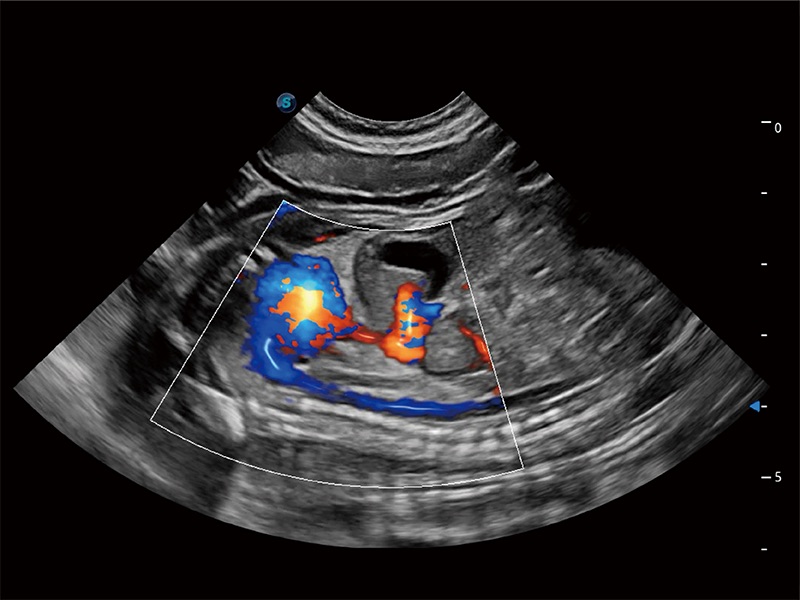

Ausgestattet mit dem gesamten Sortiment an Phased-Array-Schallköpfen von SonoScape (S1-5, 7P-A, 8P1), hochentwickelter Verarbeitungstechnologie und modernsten kardiologischen Tools bietet die ProPet-Serie Tierärzten eine umfassende ABklärung der Herz- und Myokardfunktionen.

Nutzt myokardiale Doppler-Frequenzverschiebungen zur Quantifizierung der myokardialen Gewebebewegung, wobei Rot und Blau die unterschiedlichen Bewegungsrichtungen der Herzwände darstellen. Durch die Kombination von TDI und PW lässt sich die Bewegungsbahn der Myokardwand besser erfassen.